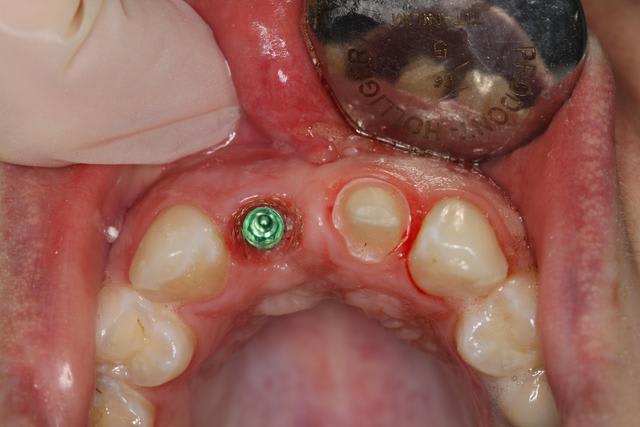

Implant posé ce matin

Le guide n'a pas été utilisé. Pas assez stable, délicat pour la visibilité, me sentais moins bien avec que sans : l'axe me paraissait pas correspondre, peur de fraiser de la résine.

Extraction simple, hauteur racine 10mm.

Alvéole propre, "boulevard" pour implanter.

Premier forage légerement en palatin, trop car petite excursion dans canal retro incisif.

Reprise de l'axe finalement au fond de l'alvéole.

Implant Legacy (ayé) 3 4,2x16mm

Bonne stabilité primaire, saignement abondant.

Utilisation pilier provisoire résine plateforme 4.7, injection de flow et polissage pour galber mais pas trop pour que la gencive revienne.

Pas de sutures, pas besoin.

Les critiques (productives et modérées) sont les bienvenues